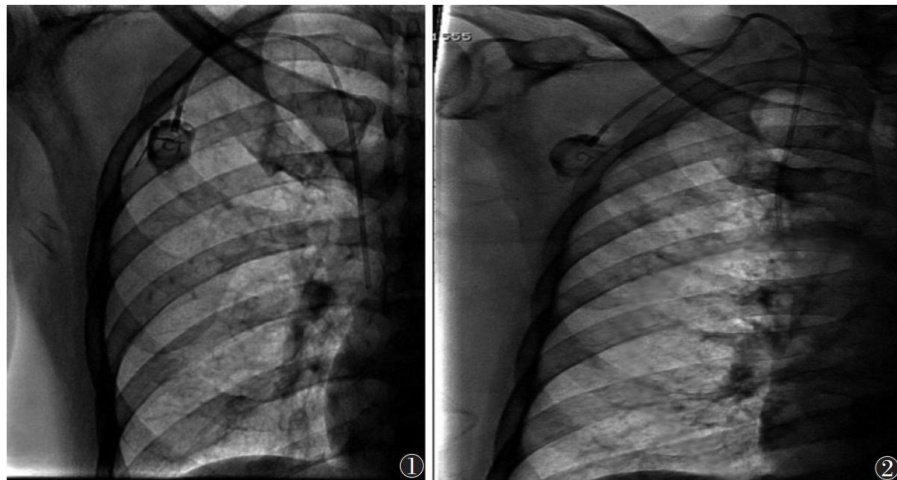

[摘要]目的:应用E-cervix宫颈弹性成像技术探讨正常妊娠孕妇不同孕期宫颈弹性参数的变化规律。方法:选取常规产检孕妇185例行E-cervix宫颈弹性成像,随访排除早产8例、胎儿严重畸形3例,最终纳入174例,其中妊娠12周49例妊娠,16周24例,20周24例,24周21例,28周21例,32周18例,36周17例。记录174例的弹性对比度指数(ECI)硬度比(HR)宫颈内口应变平均值(IOS)、宫颈外口应变平均值(EOS)、宫颈内外口应变比值(IOS/EOS)等宫颈弹性参数,分析宫颈弹性参数与孕周的关系并建立回归方程。结果:随孕周增加,HR呈降低趋势,ECI、IOS、EOS、IOS/EOS均呈升高趋势(均 P<0.05 )。HR与孕周呈负相关( r=-0.175 P=0.021 ),其线性回归方程为: HR=77.409-0.234× 孕周;ECI、IOS、EOS均与孕周呈正相关 (r=0.433,0.452 0.291;均 P=0.001 ),其线性回归方程分别为:

孕周, IOS=0.160+0.004× 孕周, EOS=0.204+0.003× 孕周。结论:随妊娠进展,正常妊娠孕妇宫颈的不均质性不断增加,宫颈硬度不断降低,且以宫颈内口的硬度降低为著。